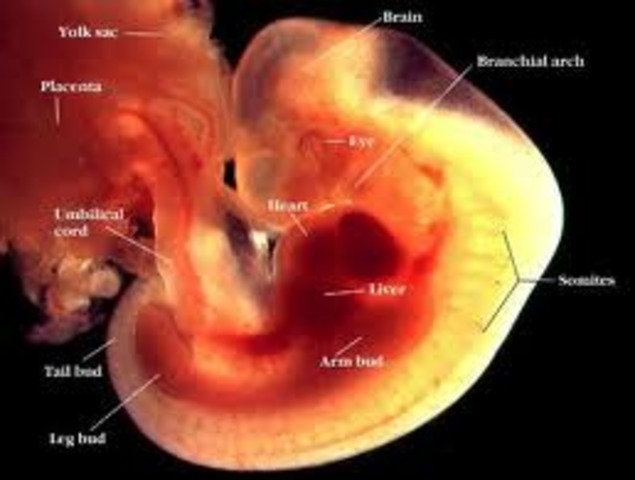

• Month 1

Month 1

• The baby is now the size of a pin head.

• The egg has attached to lining of uterus.

• This is the critical stage for brain and spinal cord development.

• Internal organs and circulatory system has begun to form.

• The heart has begun to beat.